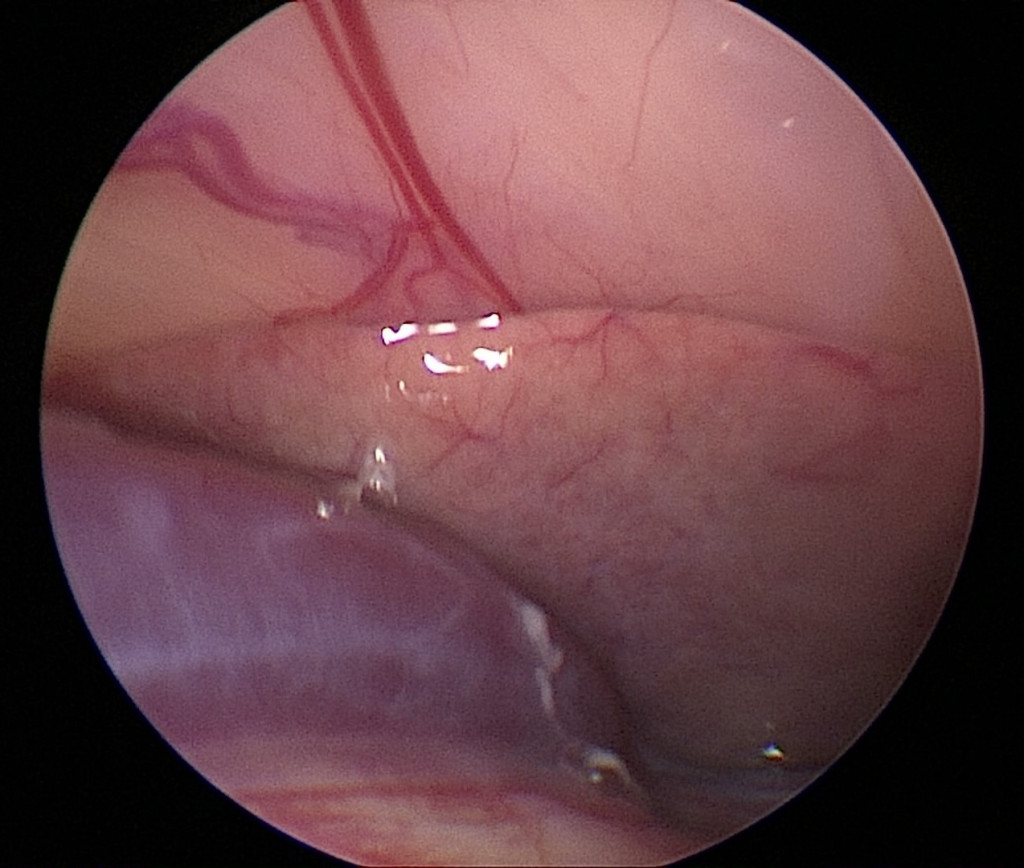

Гистологическое исследование образцов печени является золотым стандартом диагностики липидоза печени7,15,23. Для получения образцов печени у относительно крупных ящериц используется эндоскопическая целиоскопия (фото 4) У мелких и средних видов применяется целиотомия. Гистологическое подтверждение липидоза печени критически важно при подозрении на развитие фиброза, так как это напрямую влияет на прогноз заболевания. Компьютерная томография не позволяет оценить степень фиброза печени3.